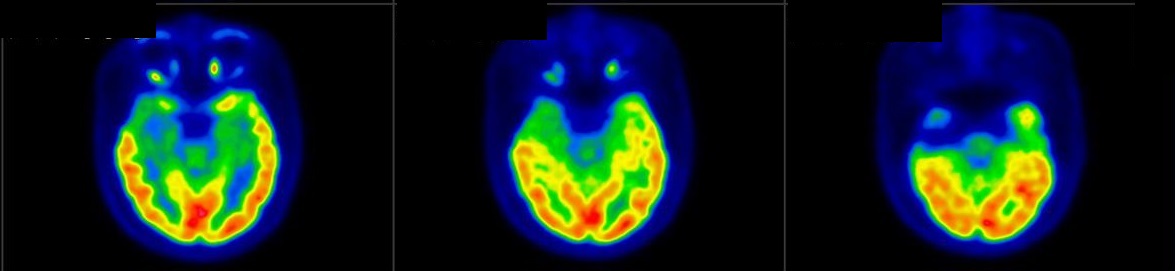

脑神经内分泌肿瘤

双示踪剂PET/CT (F-18 FDG及Ga-68 DOTATATE) 用於评估脑神经内分泌肿瘤体内的扩散情况

![]() [F-18] FDG |

![]() [Ga-68] DOTATATE |